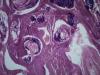

Опухоль матки |

Плоскоклеточный умереннодифференцированный рак,инвазия в железы.